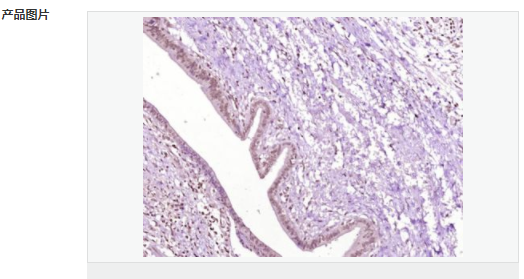

| 產(chǎn)品應(yīng)用 | WB=1:500-2000 ELISA=1:5000-10000 IHC-P=1:100-500 IHC-F=1:100-500 IF=1:100-500 (石蠟切片需做抗原修復(fù)) not yet tested in other applications. optimal dilutions/concentrations should be determined by the end user. |

| 產(chǎn)品介紹 | Acts as a growth inhibitor. Can activate TP53/p53, causes G1 arrest and collaborates with CDKN2A to restrict proliferation, but does not require either protein to inhibit DNA synthesis. Redistributes CDKN2A into the nucleoplasm. Involved in maintaining chromosomal stability. There are two isoforms. Function: Acts as a growth inhibitor. Can activate p53/TP53, causes G1 arrest and collaborates with CDKN2A to restrict proliferation, but does not require either protein to inhibit DNA synthesis. Redistributes CDKN2A into the nucleoplasm. Involved in maintaining chromosomal stability. Subunit: Interacts with CDKN2A and MDM2. Subcellular Location: Nucleus. Tissue Specificity: Widely expressed at low levels in most tissues, with highest levels in pancreas, lung and liver. Expression is decreased in primary tumors including lung, liver, breast, pancreas and kidney carcinomas, chronic lymphocytic leukemia and diffuse large B-cell lymphoma. Post-translational modifications: Ubiquitinated; mediated by MDM2 and leading to its subsequent proteasomal degradation. Similarity: Belongs to the TBRG1 family. Contains 1 FYR C-terminal domain. Contains 1 FYR N-terminal domain. SWISS: Q3YBR2 Gene ID: 84897 Database links: Entrez Gene: 84897 Human Entrez Gene: 21376 Mouse Omim: 610614 Human SwissProt: Q3YBR2 Human SwissProt: Q3UB74 Mouse Unigene: 436410 Human Unigene: 28689 Mouse Unigene: 129282 Rat Important Note: This product as supplied is intended for research use only, not for use in human, therapeutic or diagnostic applications. |